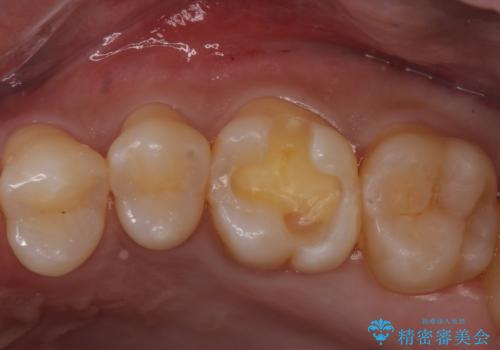

視診だけではわかりづらいですが、レントゲン画像にて昔の詰め物の下に虫歯があることがわかります。

以前樹脂を詰めた結果再び虫歯ができてしまっていることから、同じ治療は同じ結果になる可能性があるため今回はアプローチを変えてセラミックインレーで修復処置をしていくこととなりました。